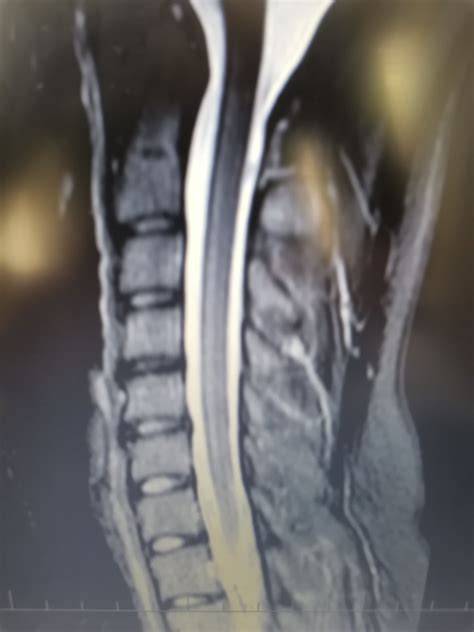

- MRI (magnetická rezonancia): Najsenzitívnejšia metóda, ktorá prináša detailné zobrazenia mozgu a chrbtice, neoceniteľné pre presnú diagnózu abnormalít.

Pri syndróme Cauda Equina sa okrem RTG kontroluje stav miechy pomocou kontrastnej látky alebo MRI. Pri Wobbler syndróme sa na zistenie stavu stavcov využíva RTG, ale na posúdenie kompresie miechy sú potrebné myelogram, myeloCT alebo MRI.